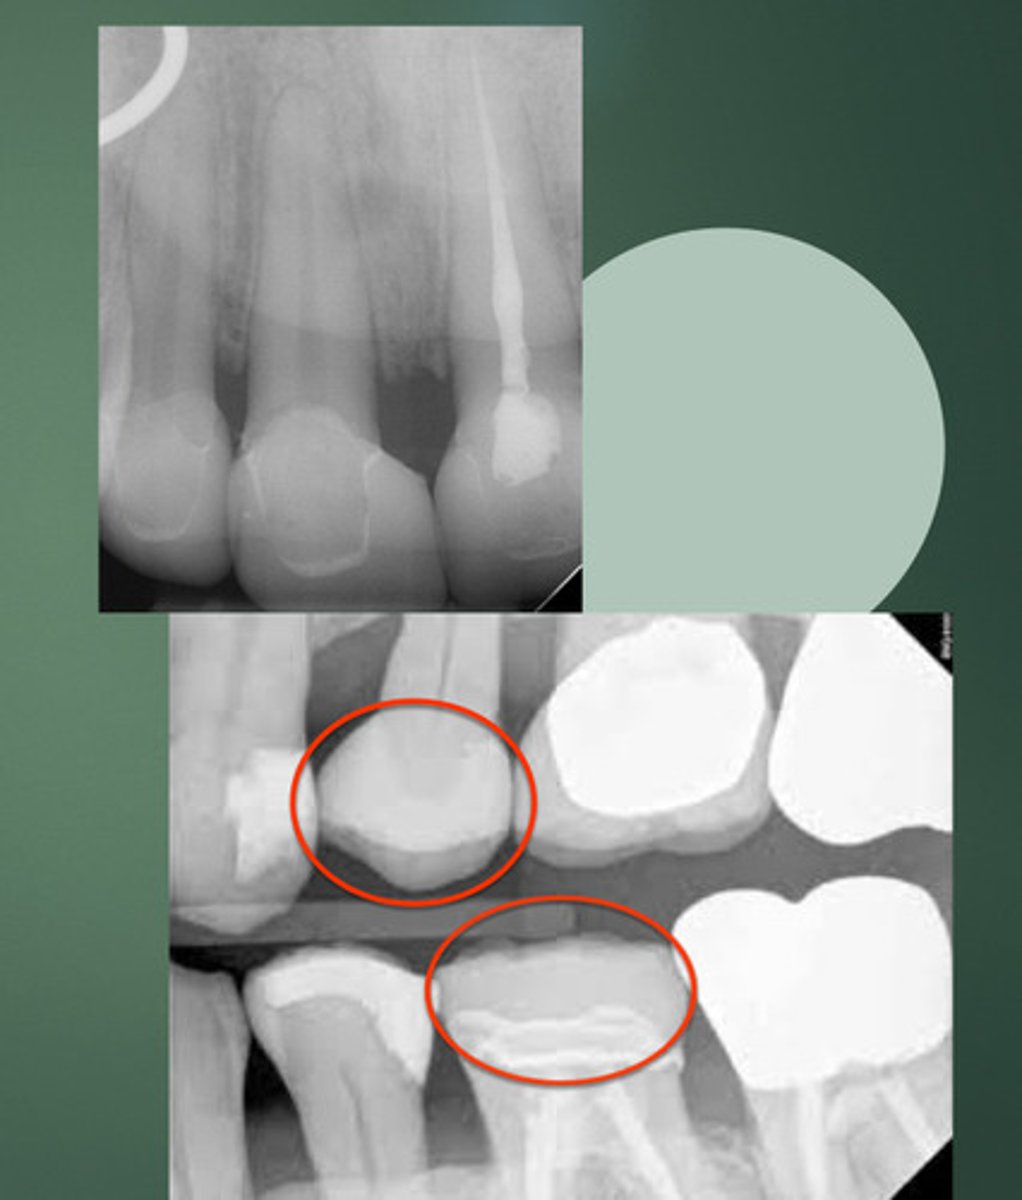

DEEP SUBGINGIVAL PREPARATION

A major contraindication for lithium disilicate is (prep)